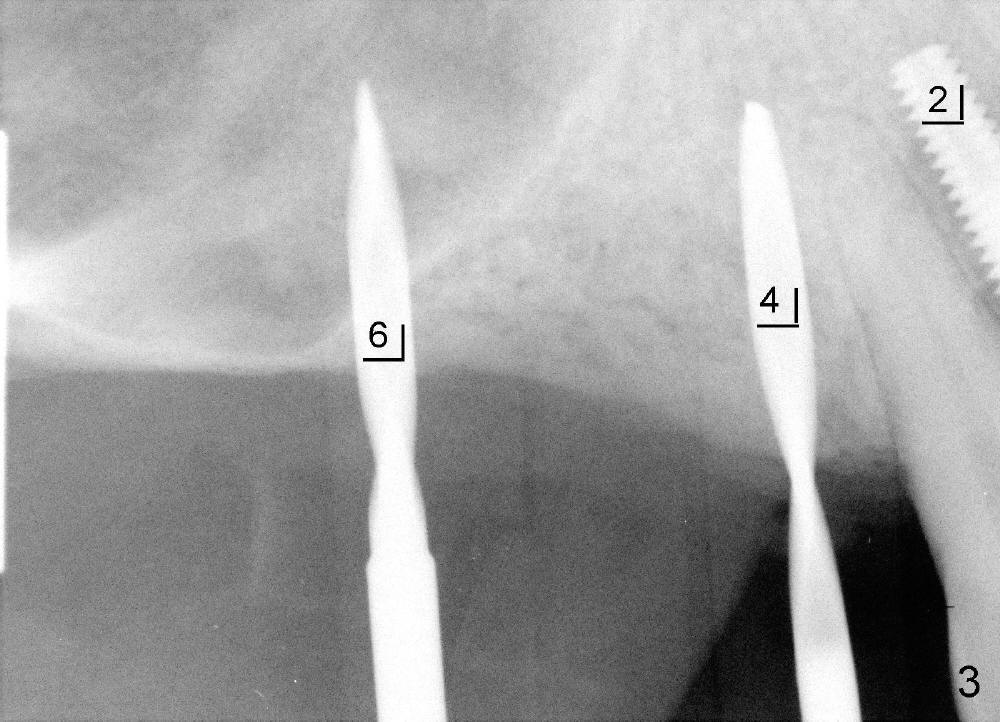

五十来岁吴先生牙周病严重(图一),尤其右上4,5,左上6,最后拔除(图二:远中面观),可见口腔卫生差。先做局部托牙,三年后又失去几个下牙,终于同意植牙。主要困难是上颌窦很低,最好先做上颌窦植骨,但是他胆子特小,多做一个手术对他来说是很大精神创伤,所以壮着胆子先做左上6植牙(图五:7x11mm,torque > 60 Ncm),虽然远中底板不可观(图五箭头之间),但是植牙很牢靠。右侧上颌窦底板更薄,估计不做上颌窦植骨不行,给他吹风说需要做一个手术才能植牙,他竟然同意。但是突然他的托牙(framework removable partial denture)断裂了,断在金属部分(major connector: anterior and posterior bars),说明他咀嚼力如此大,技工室说激光焊接没有保证。我们不得不取消上颌窦植骨,因为它会延迟植牙五六个月,所以我们再次铤而走险在右上第一双尖牙(图三:4, 4x20mm,> 60 Ncm)和第一磨牙(6, 6x11mm,> 60 Ncm)植牙,一个月后在两者之间再植入一个(图四:5,4.5x14mm,> 60 Ncm)。尽管第一磨牙植牙远中骨板相当薄(图四箭头之间),但是它很紧,可能与上颌窦底板坚硬有关。在病人多次要求下,半个月后就装上基牙(图六:2,4,5,6),放置临时牙冠,后三者连在一起(好像牙桥,增加稳定性),这样病人可以正常吃饭。一周后,侧切牙临时牙冠脱落,病人回诊所重新粘固,而右上牙桥仍稳定。